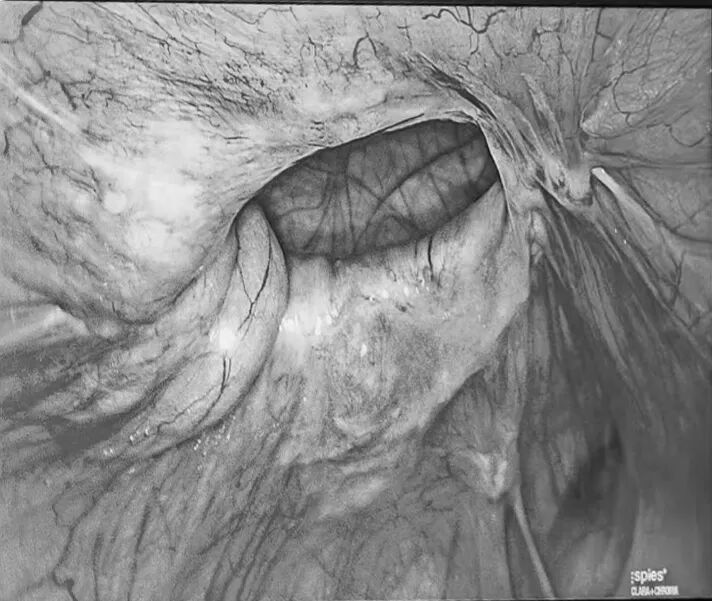

腹部CT显示:刘女士左下腹腹壁缺损直径4cm,疝囊大小8*4cm,内有腹部组织突出,诊断为腹壁疝。决定行腹腔镜下腹壁疝修补术,术中可见大网膜经腹壁缺损突出腹腔外,术中将突出腹腔的大网膜还纳回腹,用疝气钩针修补腹壁缺损后,用防粘连疝补片覆盖于缺损处,最后用疝钉固定疝补片。

▲术前可见腹壁缺损明显